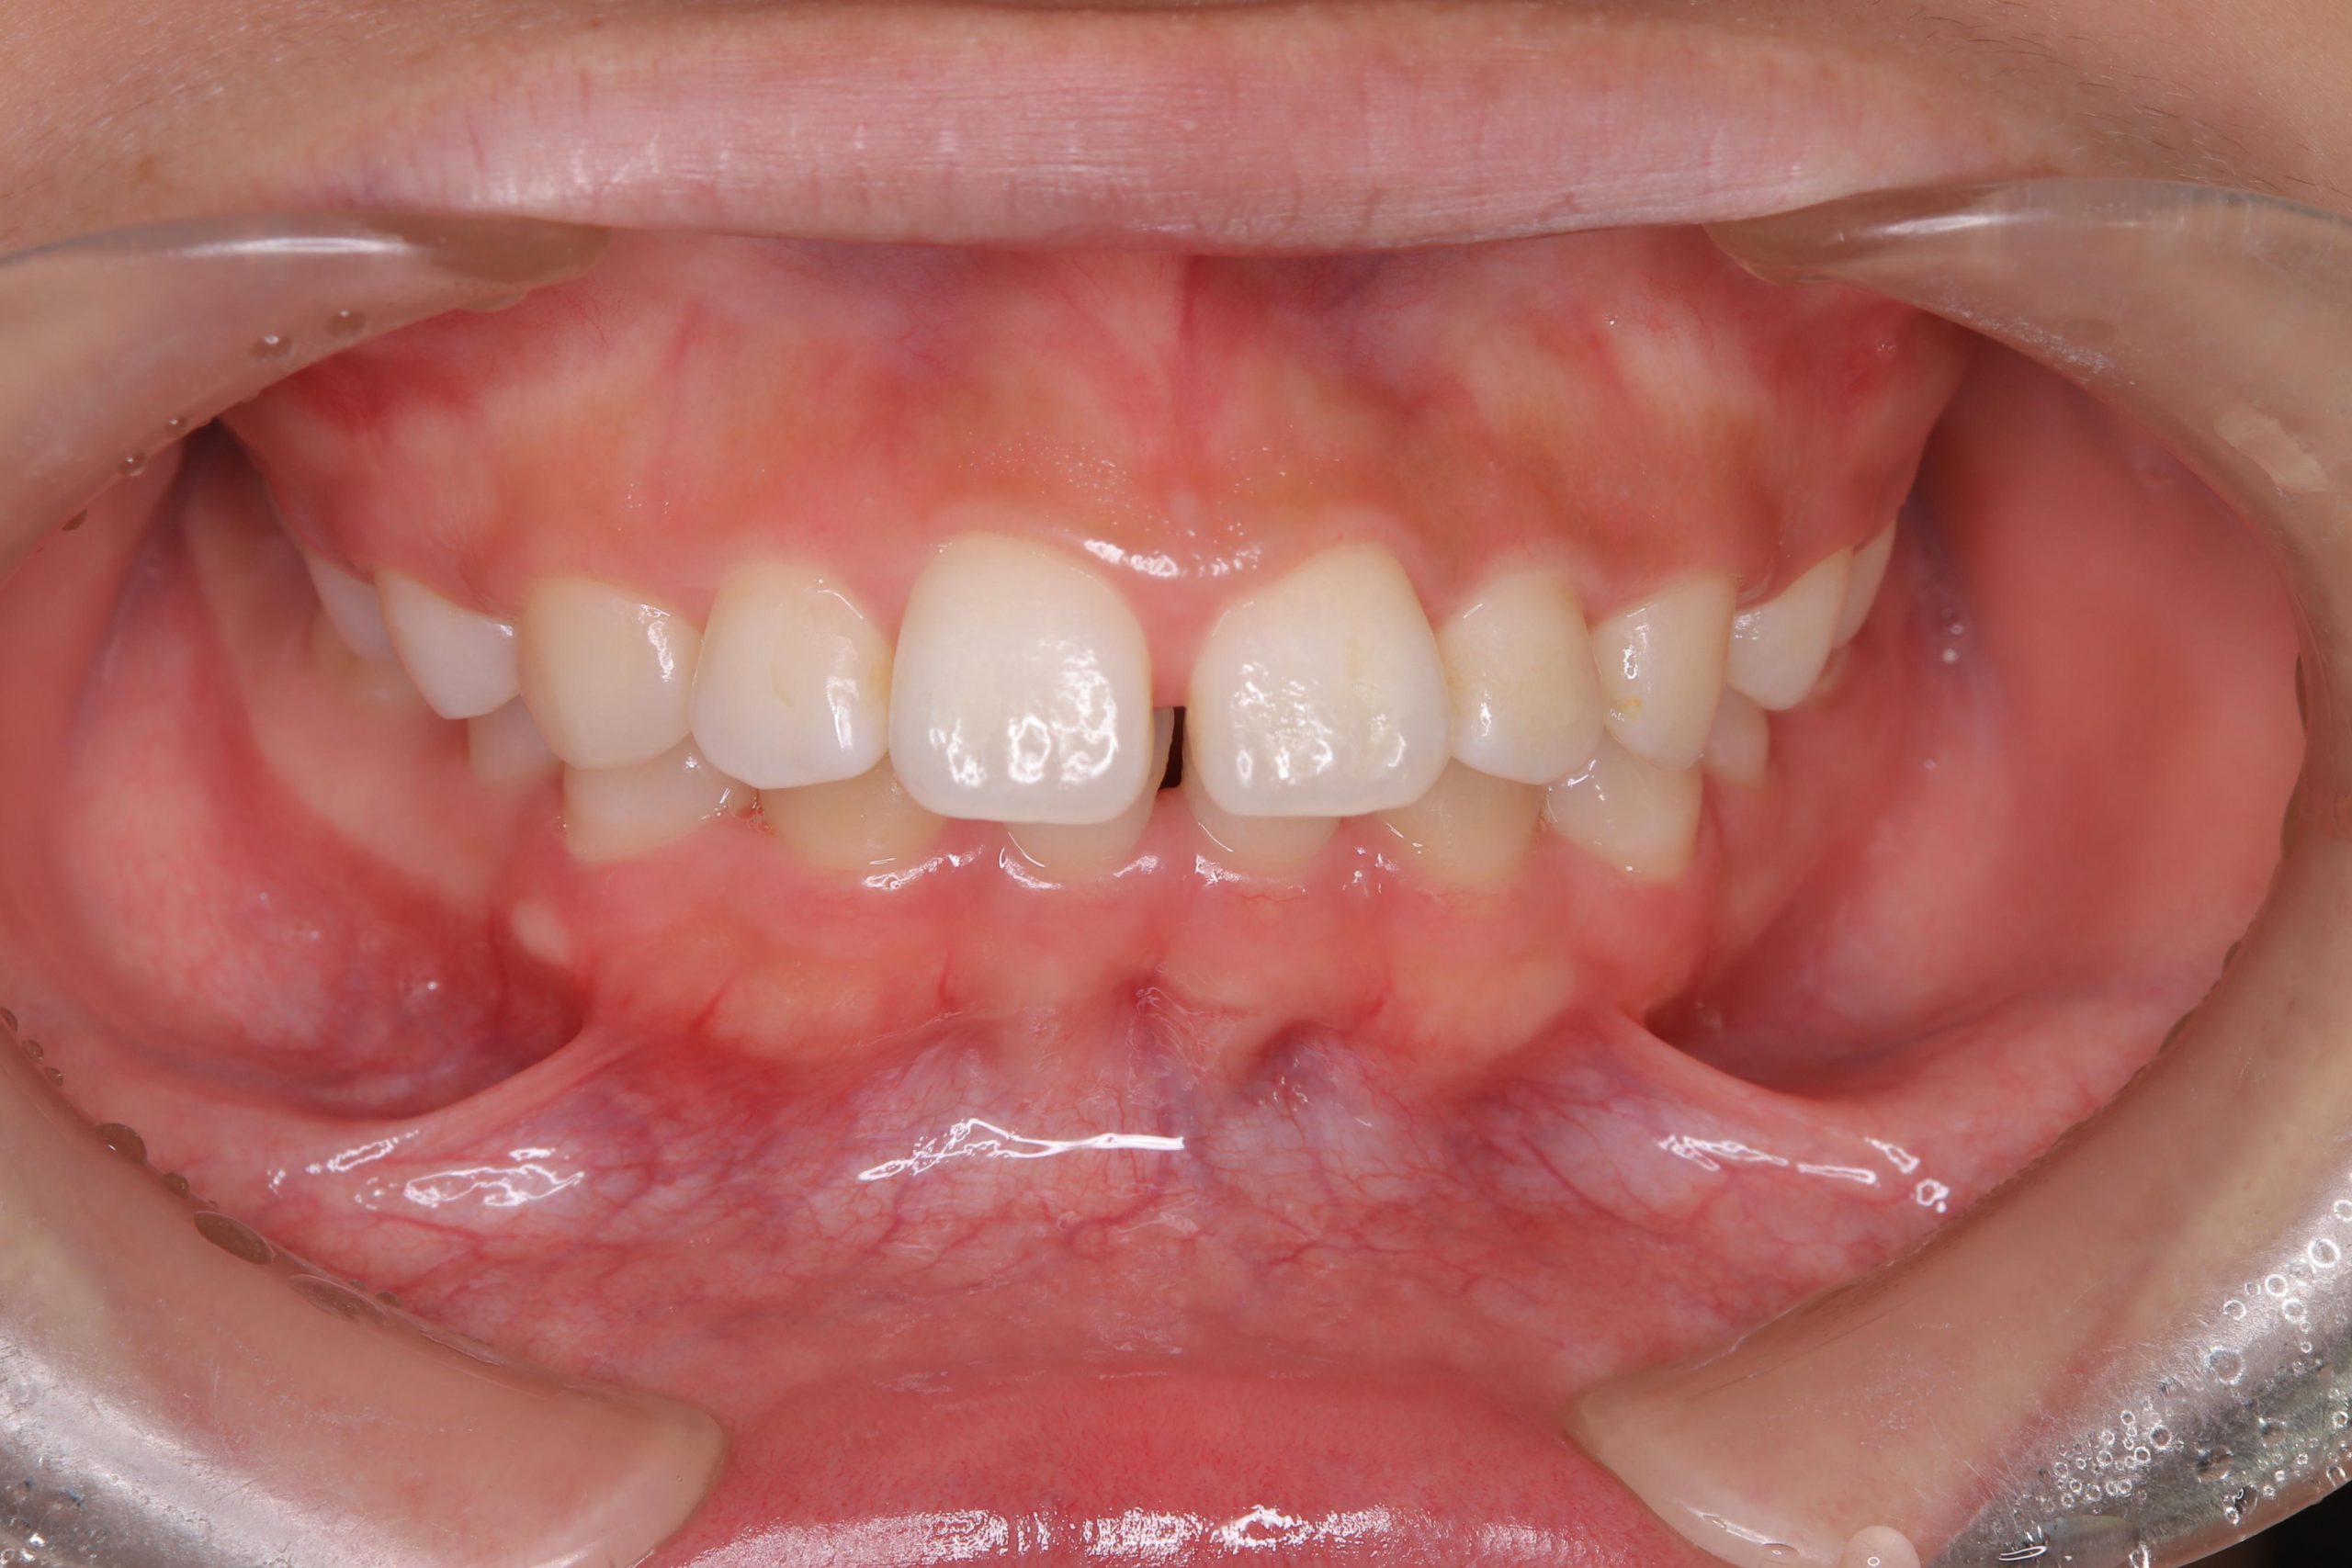

「開咬」とは、奥歯でしっかり噛んだ時に、上下の前歯が噛み合わない症状を指します。基本的に開咬とは前歯のことを指しますが、稀に奥歯でも同様の症状を起こすことがあり、前歯に空間ができる場合を「前歯部開咬」、奥歯に空間ができる場合を「臼歯部開咬」と呼びます。多くは幼少期の癖が原因によって引き起こされ、永久歯の生える時期まで指しゃぶりが続いている場合や舌癖、咬唇癖などの影響によって問題が生じます。また、顎の成長に問題があって開咬が生じる場合もあります。

この方は、開咬により前方に突出した上顎前歯と、下顎前歯の間に、下の唇が入り込んでしまうことにより、上顎前歯の前突(出っ歯)がより大きくなってしまっており、口唇をしっかり閉じようとしても歯が見えてしまうような状態でした。

この方はまだ20代の方ですが、全体的に歯肉の炎症が強く、軽度~中程度の深さのポケットも形成されておりました。

口腔内写真でも前歯部の歯肉が腫れているのがわかると思います。